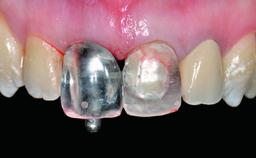

Abutment Type CAD/CAM

Retention Cemented, with prosthesis margin < 3mm submucosal Cemented, with prosthesis margin < 3mm submucosal

Provisional Implant-Supported Prosthesis Prosthodontic margin > 3 mm apical to mucosal margin Prosthodontic margin > 3 mm apical to mucosal margin